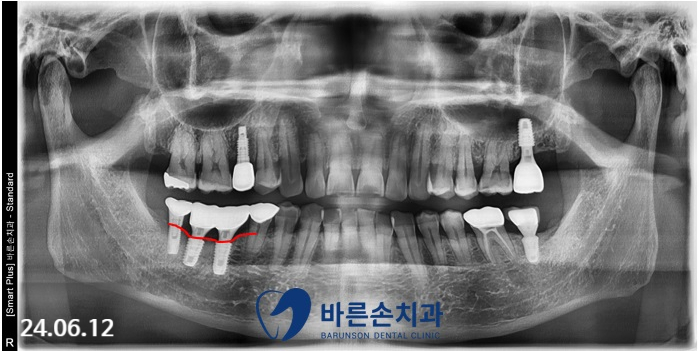

우측 아래 임플란트 2개(노란 화살표)가

임플란트 주위염으로 인해

치조골이 내려가 있습니다.

치료 전